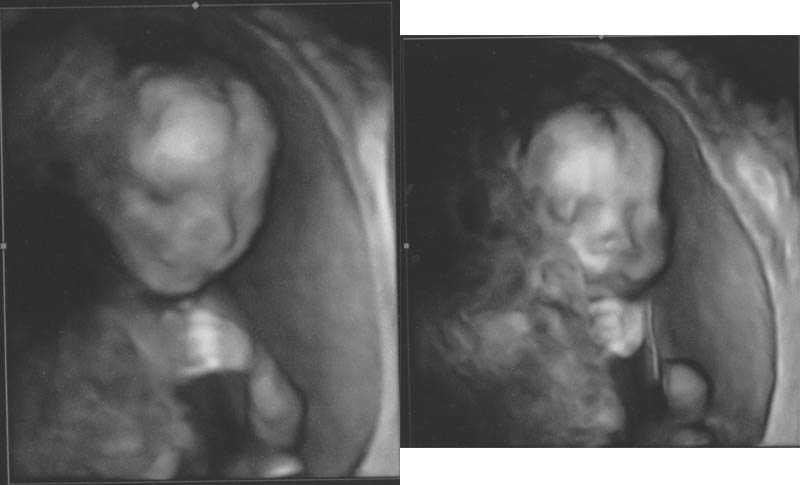

20 Weeks (3D Imaging!)

16 Weeks (3D Imaging!)